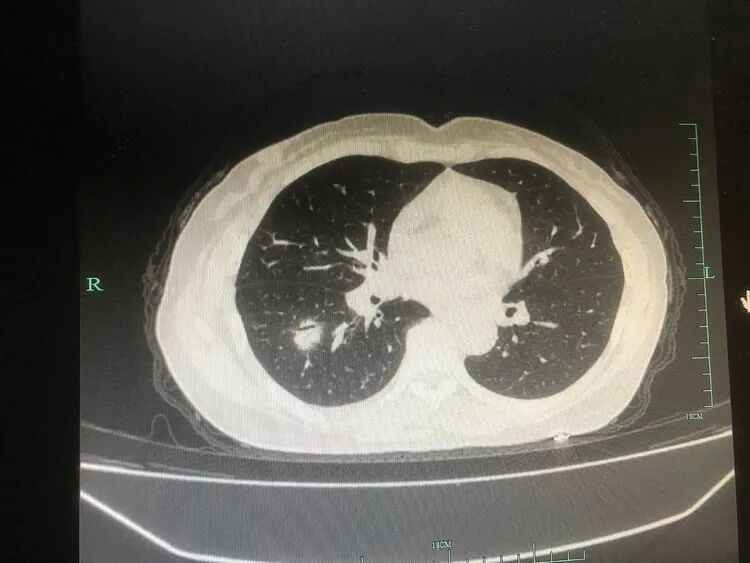

患者,楊某某,中年女性,既往有“風(fēng)濕性關(guān)節(jié)炎”病史,此次因“發(fā)熱、咳嗽2天”于2021-12-12晚入住我科;入院胸部CT提示右肺下葉結(jié)節(jié)影及大片實(shí)變影。

次日患者仍高熱、頭暈乏力,但咳嗽咳痰不明顯,通過(guò)細(xì)讀胸部CT及影像特點(diǎn),陳蒼宋主治醫(yī)師考慮不典型菌感染,再次追問(wèn)病史,了解到患者近期有禽類接觸史,因此,高度懷疑鸚鵡熱衣原體感染,在與呼吸與危重癥醫(yī)學(xué)科主任張君利、副主任陶毅強(qiáng),主治中醫(yī)師賀潔討論后,建議完善相關(guān)檢查,如支氣管鏡檢查等,并于治療上加用莫西沙星覆蓋病原菌。